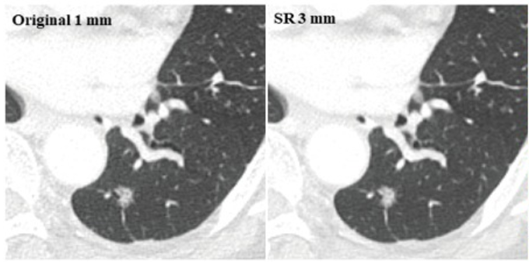

초해상도는 영상 슬라이스 두께가 서로 다른 CT 이미지를 더 얇은 두께로 변환해 영상의 일관성과 정밀도를 높이는 기술이다. 뷰노는 최근 이 기술을 '재구성된 영상군에 기초한 영상 제공 방법 및 이를 이용한 장치'로 일본 특허를 취득했다.

일본 특허는 여러 장의 단층 영상으로 구성된 CT 영상에서 영상 슬라이스 간 간격을 의미하는 영상의 두께를 5㎜, 3㎜, 1㎜에서 자유롭게 전환할 수 있는 인터페이스를 전달하는 방법을 핵심으로 한다.

실제로 영상의학 분야에서 가장 권위있는 학술지인 'Radiology'에 발표된 내용을 보면 초해상도 알고리즘을 통해 두께를 변환한 경우 3㎜와 5㎜ 모두에서 폐결절 탐지의 민감도가 개선된 것으로 나타났다.

여기에 '대한영상의학회(KJR)'에서 발표된 내용에 따르면 이 알고리즘으로 다양한 두께의 흉부 CT 슬라이스를 1㎜로 변환했을 때 기존 1㎜ 슬라이스와 유사한 수준의 라디오믹 특징(Radiomic Feature)의 재현성(Reproducibility)을 보였다.